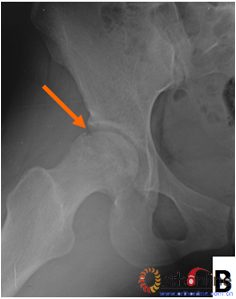

图3 各型坏死打压植骨的结果,(A)Ⅰ型(右侧)和Ⅱ型(左侧)术前MRI显示外侧柱存留;(B)术后7年随访,股骨头维持外形,关节功能好;(C)Ⅲ型(双侧)术前MRI显示外侧柱破坏;(D)术后5年,右侧股骨头维持外形,左侧塌陷

Fig 3 The results of different osteonecrotic type by impacting bone graft,(A)Type Ⅰ(right),type Ⅱ(left) MRI showed the preservation of the lateral pillar preoperatively; (B) Seven years after operation, the femoral head still maintain sphere, hip function is excellent; (C) Type Ⅲ (both side) MRI showed the involved of lateral pillar by necrosis; (D)Five years after operation, the femoral head still maintain sphere in right side, collapse occurred in left side.